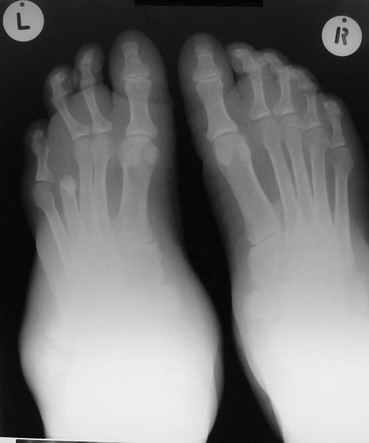

Мелореостоз

Под названием "мелореостоз" описано около 50 случаев врожденного заболевания скелета, выражающегося в совершенно

своеобразном одностороннем остеосклерозе костей одной только конечности. Можно не сомневаться в том, что

мелореостоз встречается далеко не редко; мы наблюдали свыше 20 случаев. Вполне естественно, что отдельные новые

казуистические наблюдения, не вносящие в науку никаких новых фактов и не возбуждающие новых мыслей и обобщений,

остаются неопубликованными.

Остеосклероз при этом заболевании захватывает не всю кость по окружности, а простирается слегка волнистой

полосой вдоль длинной оси конечности (рис. 223, К), переходя через линию суставов на другие кости. Таким образом,

может оказаться пораженной целая верхняя или нижняя конечность или больший или меньший ее периферический участок,

например, часть лопатки, полуцилиндр плечевой кости, часть цилиндра лучевой кости и скелет II пальца вместе с

лежащими по этой оси участками запястных костей или же часть - медиальная или латеральная - бедренной,

болынеберцовой кости с продолжением и расширением процесса на предплюсневые и плюсневые кости и соответствующие

по длиннику фаланги одного или нескольких, но никогда не всех пальцев. Описавшие эту болезнь в 1922 г. Жоани

(Joanny) и Лери (Leri) сравнивают остеосклеротические полосы с картиной, напоминающей стекающий со свечи и

застывающий стеарин или воск, отсюда и название "мелореостоз" - "стекающая вдоль конечности кость".